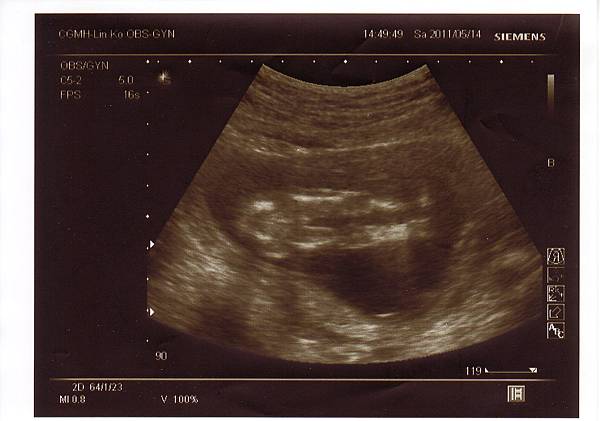

2011.05.14 第二次產檢,醫生雖然不是很確定但說女寶寶的機率比較大,

不論是否為女寶,媽咪只希望你是個健康的寶寶就好了